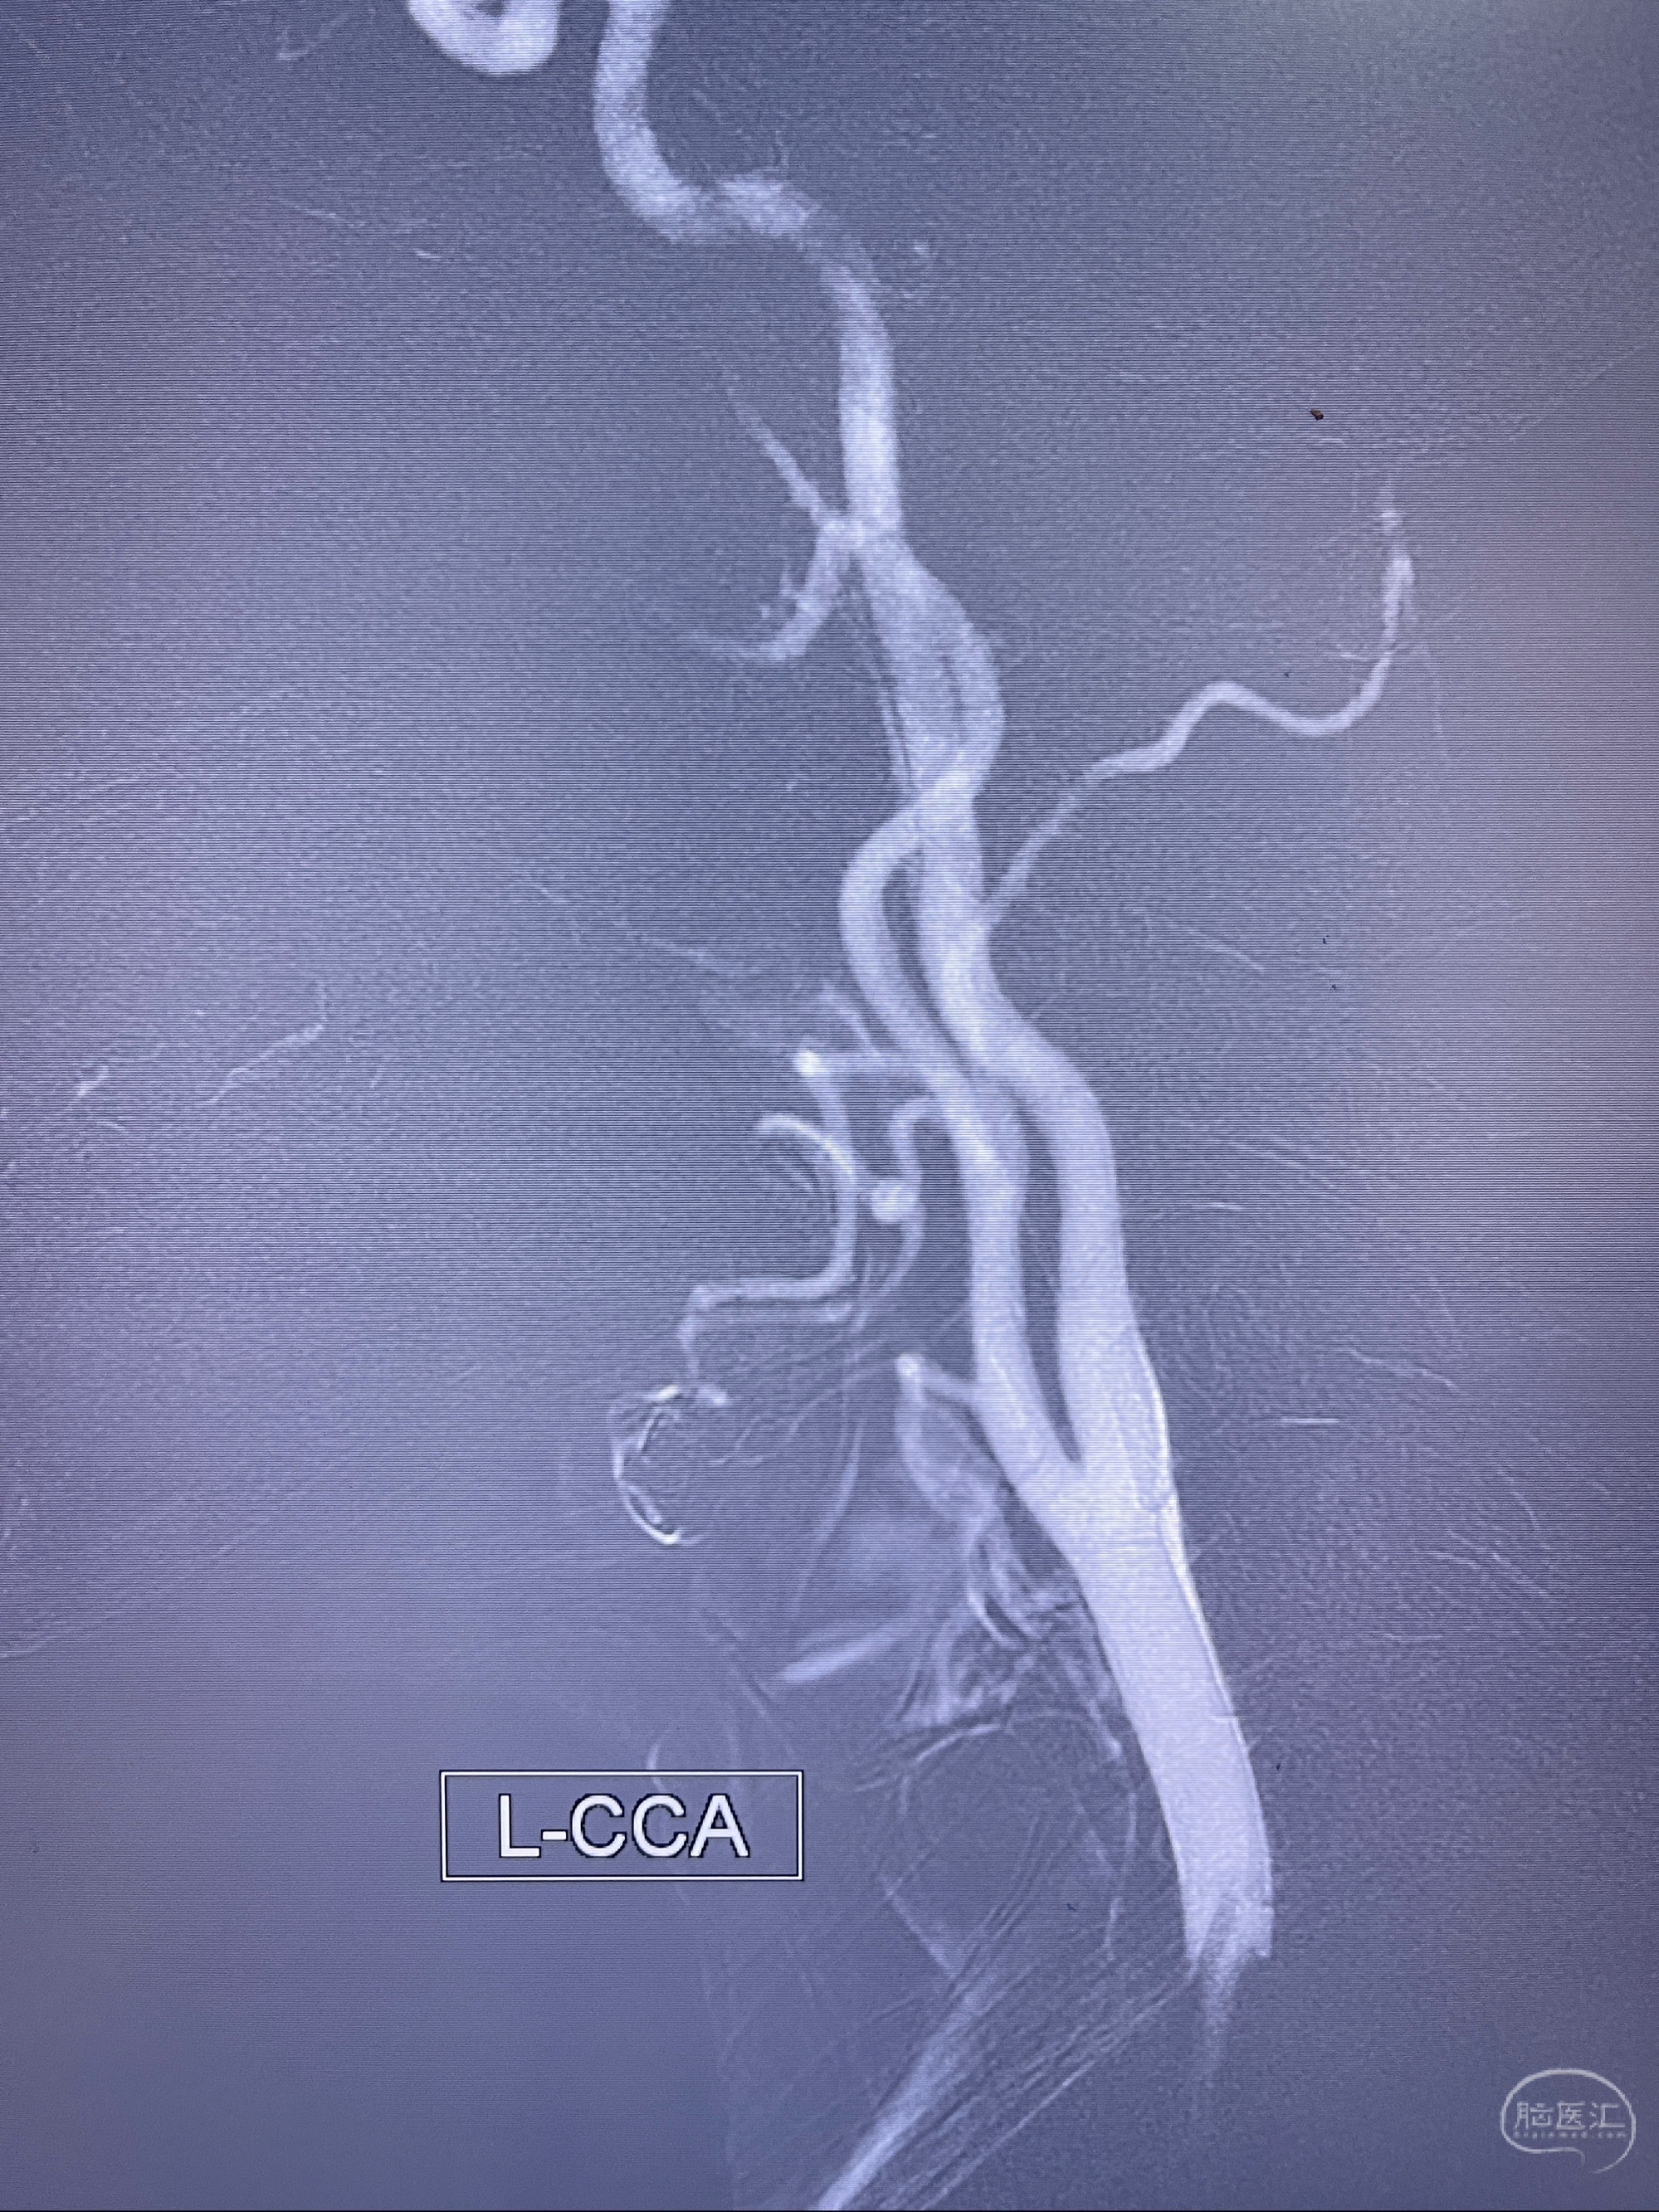

2023.07.25 泰州市人民医院查头颅CTA提示右侧C6段瘤样突起,建议DSA检查;

CTA示:右侧颈内动脉C6段见指向下方的突起,余左侧颈内动脉、双侧椎动脉、大脑前动脉、大脑中动脉、大脑后动脉及基底动脉走形正常,未见明显扩张及狭窄,局部未见明显瘤样扩张。

2023-07-27全脑血管造影:双侧颈内动脉眼动脉段动脉瘤,右侧较大